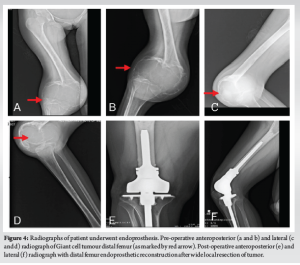

The average age of the patients in the study was 35.69 ± 12.75 years (range: 18–69 years). There were 18 men and 13 women. The distal femur were 12 and proximal tibia were 19 involved in our study. 29 patients had a primary GCT while 2 patients had a recurrent GCT. The tumors were staged radiologically using the Campanacci grading. There were eleven cases of Grade II tumor and twenty cases of Grade III tumor. Five patients had pathological fracture at presentation. In our study, 6 underwent the sandwich procedure using PMMA as a void filler (Fig. 1), 10 underwent extended curettage and autologous bone graft (Fig. 2), 11 underwent extended curettage and morselized allograft (Fig. 3), and 4 patients underwent endoprosthesis (Fig. 4).

The aim of this study was to evaluate the clinical and radiological outcomes in patients with GCTs around the knee who underwent surgical treatment, with a minimum follow-up period of 1 year. GCT is a benign primary bone tumor that is locally aggressive but has the potential for malignant metastasis [3-7]. It accounts for 5–7% of all primary bone tumors and approximately 20% of benign bone tumors [8]. Typically, GCTs occur in the epiphyseal-metaphyseal regions of long bones and predominantly affect individuals aged 20–40 years. Our study included 31 patients with GCTs around the knee. Of these, 19 patients (61%) had tumors in the proximal tibia, while 12 patients (39%) had tumors in the distal femur. A significant proportion, 20 patients (64.5%), fell within the 20–40 age group. As per to literature, it has shown more female preponderance than male [9]. Our study had involved 18 males (58%) making it greater than females in the study period, but it was statistically not significant. GCT can present with a vast variety of symptoms, for example, pain, swelling, decreased joint mobility, fracture of involved bone, neurovascular involvement of the limb, or accidental finding while routine check-up. Most of the patients enrolled in our study presented with above above-listed complaints but 5 (16.12%) of 31 patients presented with pathological fracture around knee. Evaluation for GCT involves non-invasive and invasive modalities. Initial radiographs and MRI are usually performed where it appears as a pure lytic cystic lesion that frequently, though not always, grows eccentrically in the epiphysio-metaphyseal area of the bone. The bone’s afflicted region may enlarge, while the cortical bone may become thinner. In an advanced stage, the GCT breaks through the cortex, and the production of spicules around the tumour occurs in the absence of periosteal response [5]. The MRI indicators of GCT include evidence of tissue haemorrhages, high contrast medium enhancement, and high signal intensity in T2-weighted images [10]. As per the description given for GCT [11], 11 (35.48%) patients belonged to grade II, and 20 (64.52%) patients were of grade III in our conducted study. Systematic analysis of existing literature suggests that Campanacci Grade III GCTs are commonly associated with pathological fractures at presentation [12]. Of the 5 pathological fractures in our study, all belonged to Campanacci grade III. Extended curettage has been used to treat GCT for a long time [6]. The tumor can be removed either by broad excision or curettage with or without local adjuvants depending on the involvement of the articular surfaces. In one of our previous published study of synchronous GCT around talus, we have performed extended curettage and allograft to treat the bone defect and provide mechanical stability and there was no local recurrence of tumor or altered joint functionality [13]. However, the question of restoring bone abnormalities has been divisive ever since. Several studies have shown that bone cement or bone transplants can be used to treat a bone deficit. There are currently no high-quality comparison studies in the literature that expressly assess the GCT around the knee joint and include a specific Campanacci grading. In our study, 7 patients underwent extended curettage and bone grafting, 6 patients underwent wide excision and endoprosthesis. Of the 25 patients for bone defect after curettage, 12 patients underwent sandwich procedure, 7 underwent wide excision and autograft from iliac crest or iliac crest and fibular strut and 6 underwent bone cement. Bone cement as an adjuvant with bone graft was used in all the extended curettage patients for deficit bone. The use of bone cement as an adjuvant reduced the local recurrence rate in individuals who had curettage to 12–27% [14]. The result of a methodical effort to reduce recurrence rates is the use of a wide variety of adjuvants after curettage, such as the local application of phenol, PMMA, liquid nitrogen, or a combination of many choices. Probably, the most well-established treatment to employ after curettage is phenol and PMMA. In our study, we included only primary or recurrent GCTs belonging to grade II or III and reported local recurrence only in 1 patient who underwent sandwich procedure after 1 year of follow-up. Post-operative infection is one of the common complications noted in most of the surgeries. Here, in case of GCTs around knee, infection rate is compared between intralesional curettage and wide excision studies conducted in past [6]. They reported an infection rate of 5.8%. A systematic analysis that included one of the largest series of wide resections for GCTs reported an infection rate of 6.3% [12]. We reported no infection around knee in our study. The need for revision surgery is needed in case of local recurrence, infection, or implant-related complications. A systematic analysis [12] reported that revision surgeries were frequently required following endoprosthesis, with rates exceeding 40% in some series. In our retrospective study, there was no revision surgery needed. The MSTS rating scores reported in the various series frequently represented exceptional or excellent functional results [12]. In our study, MSTS mean was 28.91 for sandwich procedure, 29.28 for extended curettage and bone graft, 26.33 for extended curettage and bone cement, and 27.83 for endoprosthesis.